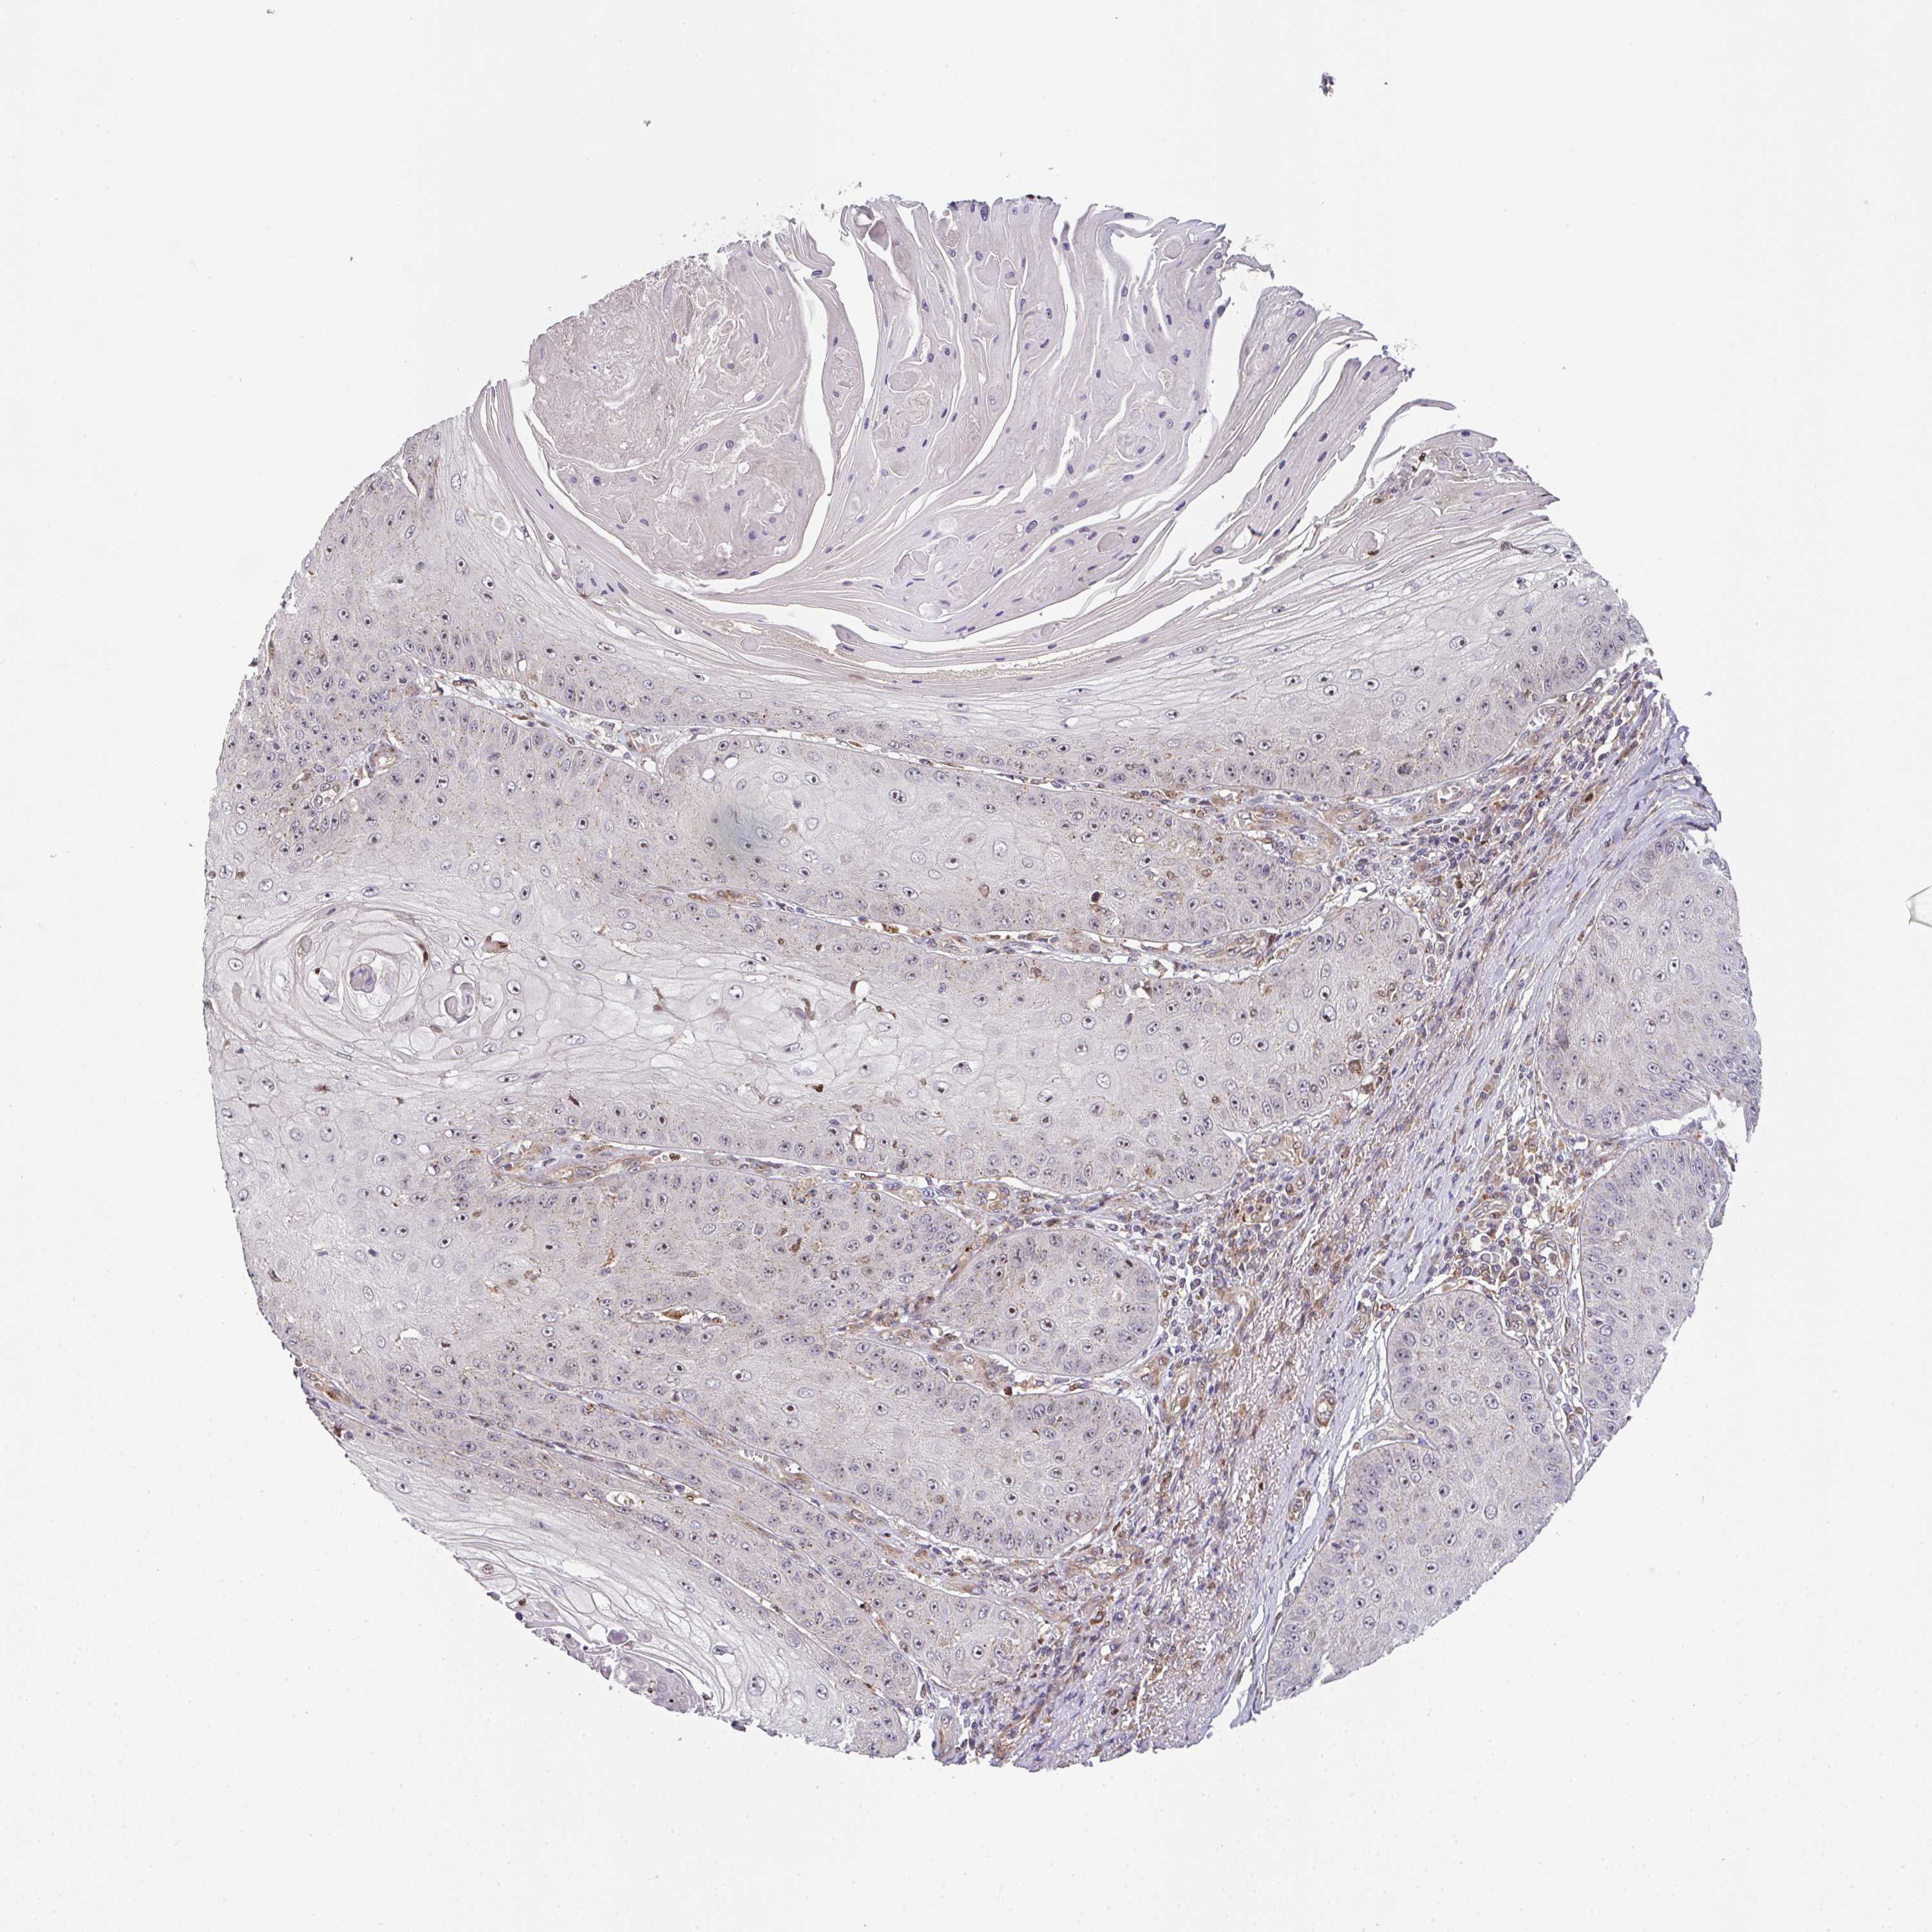

SKIN CANCER - Protein expressioni

A mouse-over function shows sample information and annotation data. Click on an image to view it in a full screen mode. Samples can be filtered based on level of antibody staining by selecting one or several of the following categories: high, medium, low and not detected. The assay and annotation is described here.

Antibody staining in the annotated cell types in the current human tissue is reported as not detected, low, medium, or high, based on conventional immunohistochemistry profiling in selected tissues. This score is based on the combination of the staining intensity and fraction of stained cells.

Each image is clickable and will lead to virtual microscopy that enables deeper exploration of all samples and also displays staining intensity scores, fraction scores and subcellular localization as well as patient and tissue information for each sample.

Antibody HPA037890

Basal cell carcinoma

Squamous cell carcinoma, NOS